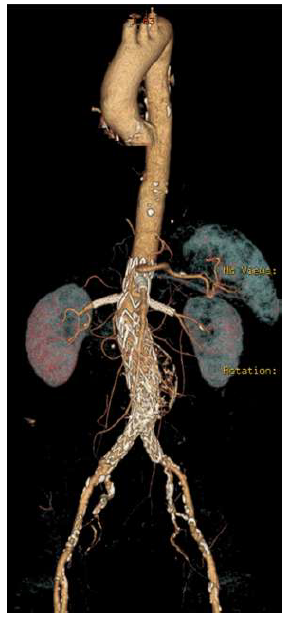

The patient was discharged home on the ninth postoperative day. A six-month follow-up CTA confirmed the AAA's exclusion, with maintained patency of all visceral vessels and no evidence of endoleak (Figure 3). No further clinical events were related to the AAA or the PMEG.

Complete exclusion of the juxta-renal aneurysm is noted, with no evidence of endoleak, and patency of all target visceral vessels is maintained.